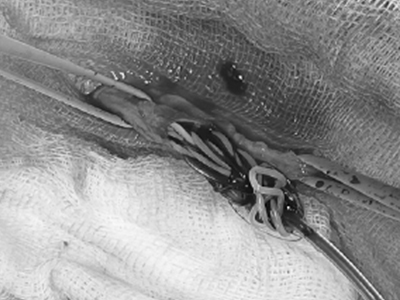

심장사상충 제거술 (Heartworm Removal) 중증 케이스

심장사상충 제거술은 중증 심장사상충 감염으로 인해 약물 치료만으로는 위험하거나 효과가 제한적인 경우 시행되는 중재적 시술입니다. 혈관 카테터를 이용해 심장 또는 폐동맥 내에 존재하는 사상충을 직접 제거함으로써 폐혈관 폐색과 급성 쇼크 위험을 줄이고, 심장 부담을 빠르게 완화하는 데 목적이 있습니다.

심장사상충 제거술 이미지 1

심장사상충 제거술

심장사상충 제거술 이미지 2

안내

환자의 상태와 심장·폐동맥 내 기생충의 위치에 따라 시술 난이도와 접근 방법이 달라질 수 있으며, 시술 전 정밀 영상 평가와 시술 후 모니터링이 필요합니다.